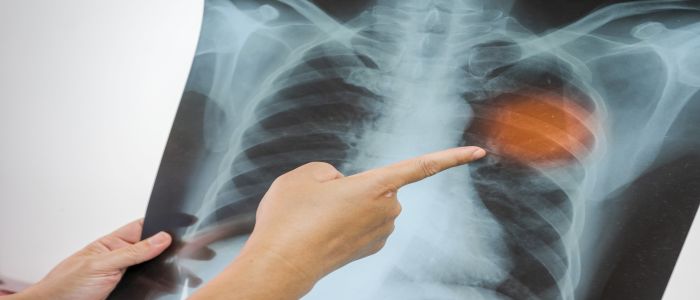

In what was one of the largest and most ambitious screening campaigns ever conducted, more than 715,000 Glasgow residents were screened with chest X-ray over a five-week period in March and April 1957. A centre with two X-ray units was erected in George Square along with 37 mobile radiography units staffed by volunteers across the city.

The researchers found that before the mass screening (1950-56), tuberculosis notification rates were declining at 2.3% per year, but rates doubled in the year of the screening (1957). After the screening, tuberculosis notification rates declined at 5.4% per year, and there were an estimated 4,599 cases averted – equivalent to 43% lower than had the screening campaign not happened. These effects were consistent across all city wards.